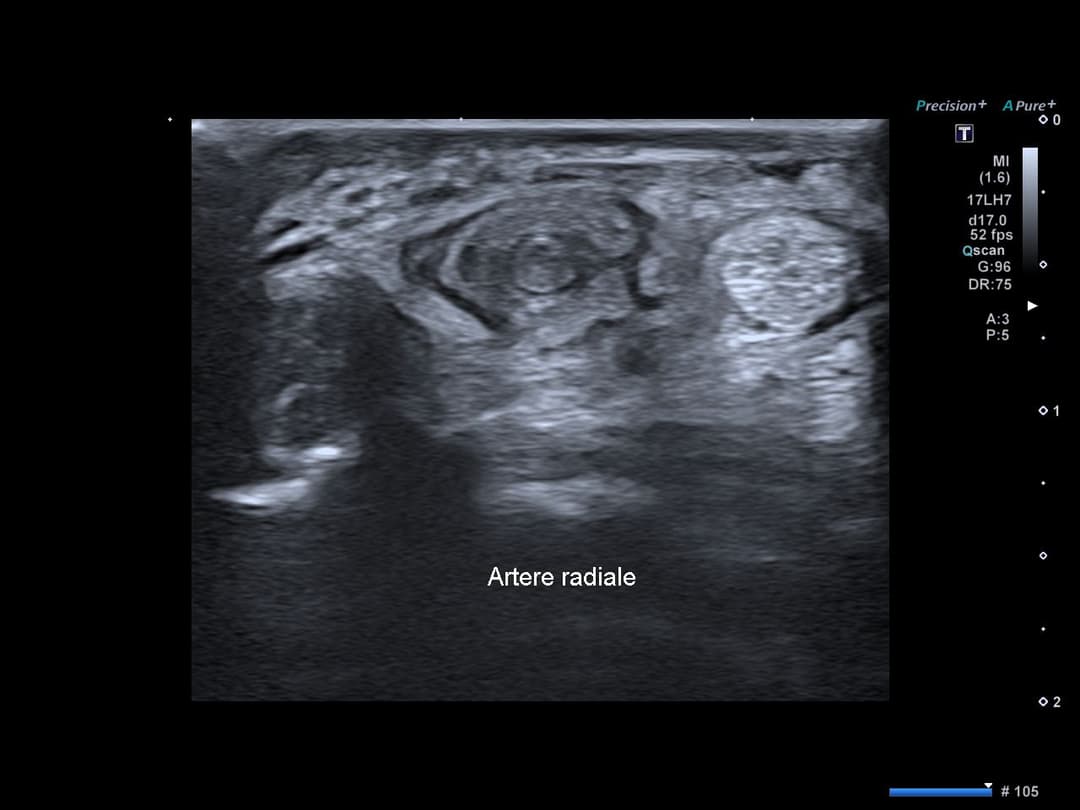

Thrombose de l'artère radiale

Thrombose complète segmentaire de l'artère radiale avec oedeme péri artériel